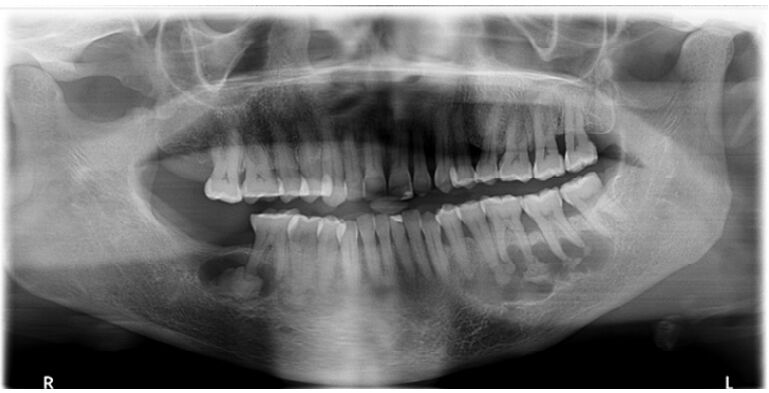

78.如圖 X 光影像所示,下列敘述何者錯誤?

(A)此 X 光影像所顯示疾病最可能是 Treacher Collins syndrome (B)左側中央,短而細的箭頭指的是 wormian bones in the occipital region (C)此 X 光影像所顯示疾病最可能是 cleidocranial dysplasia (D)右側中上,長而粗的箭頭指的是 open fontanel